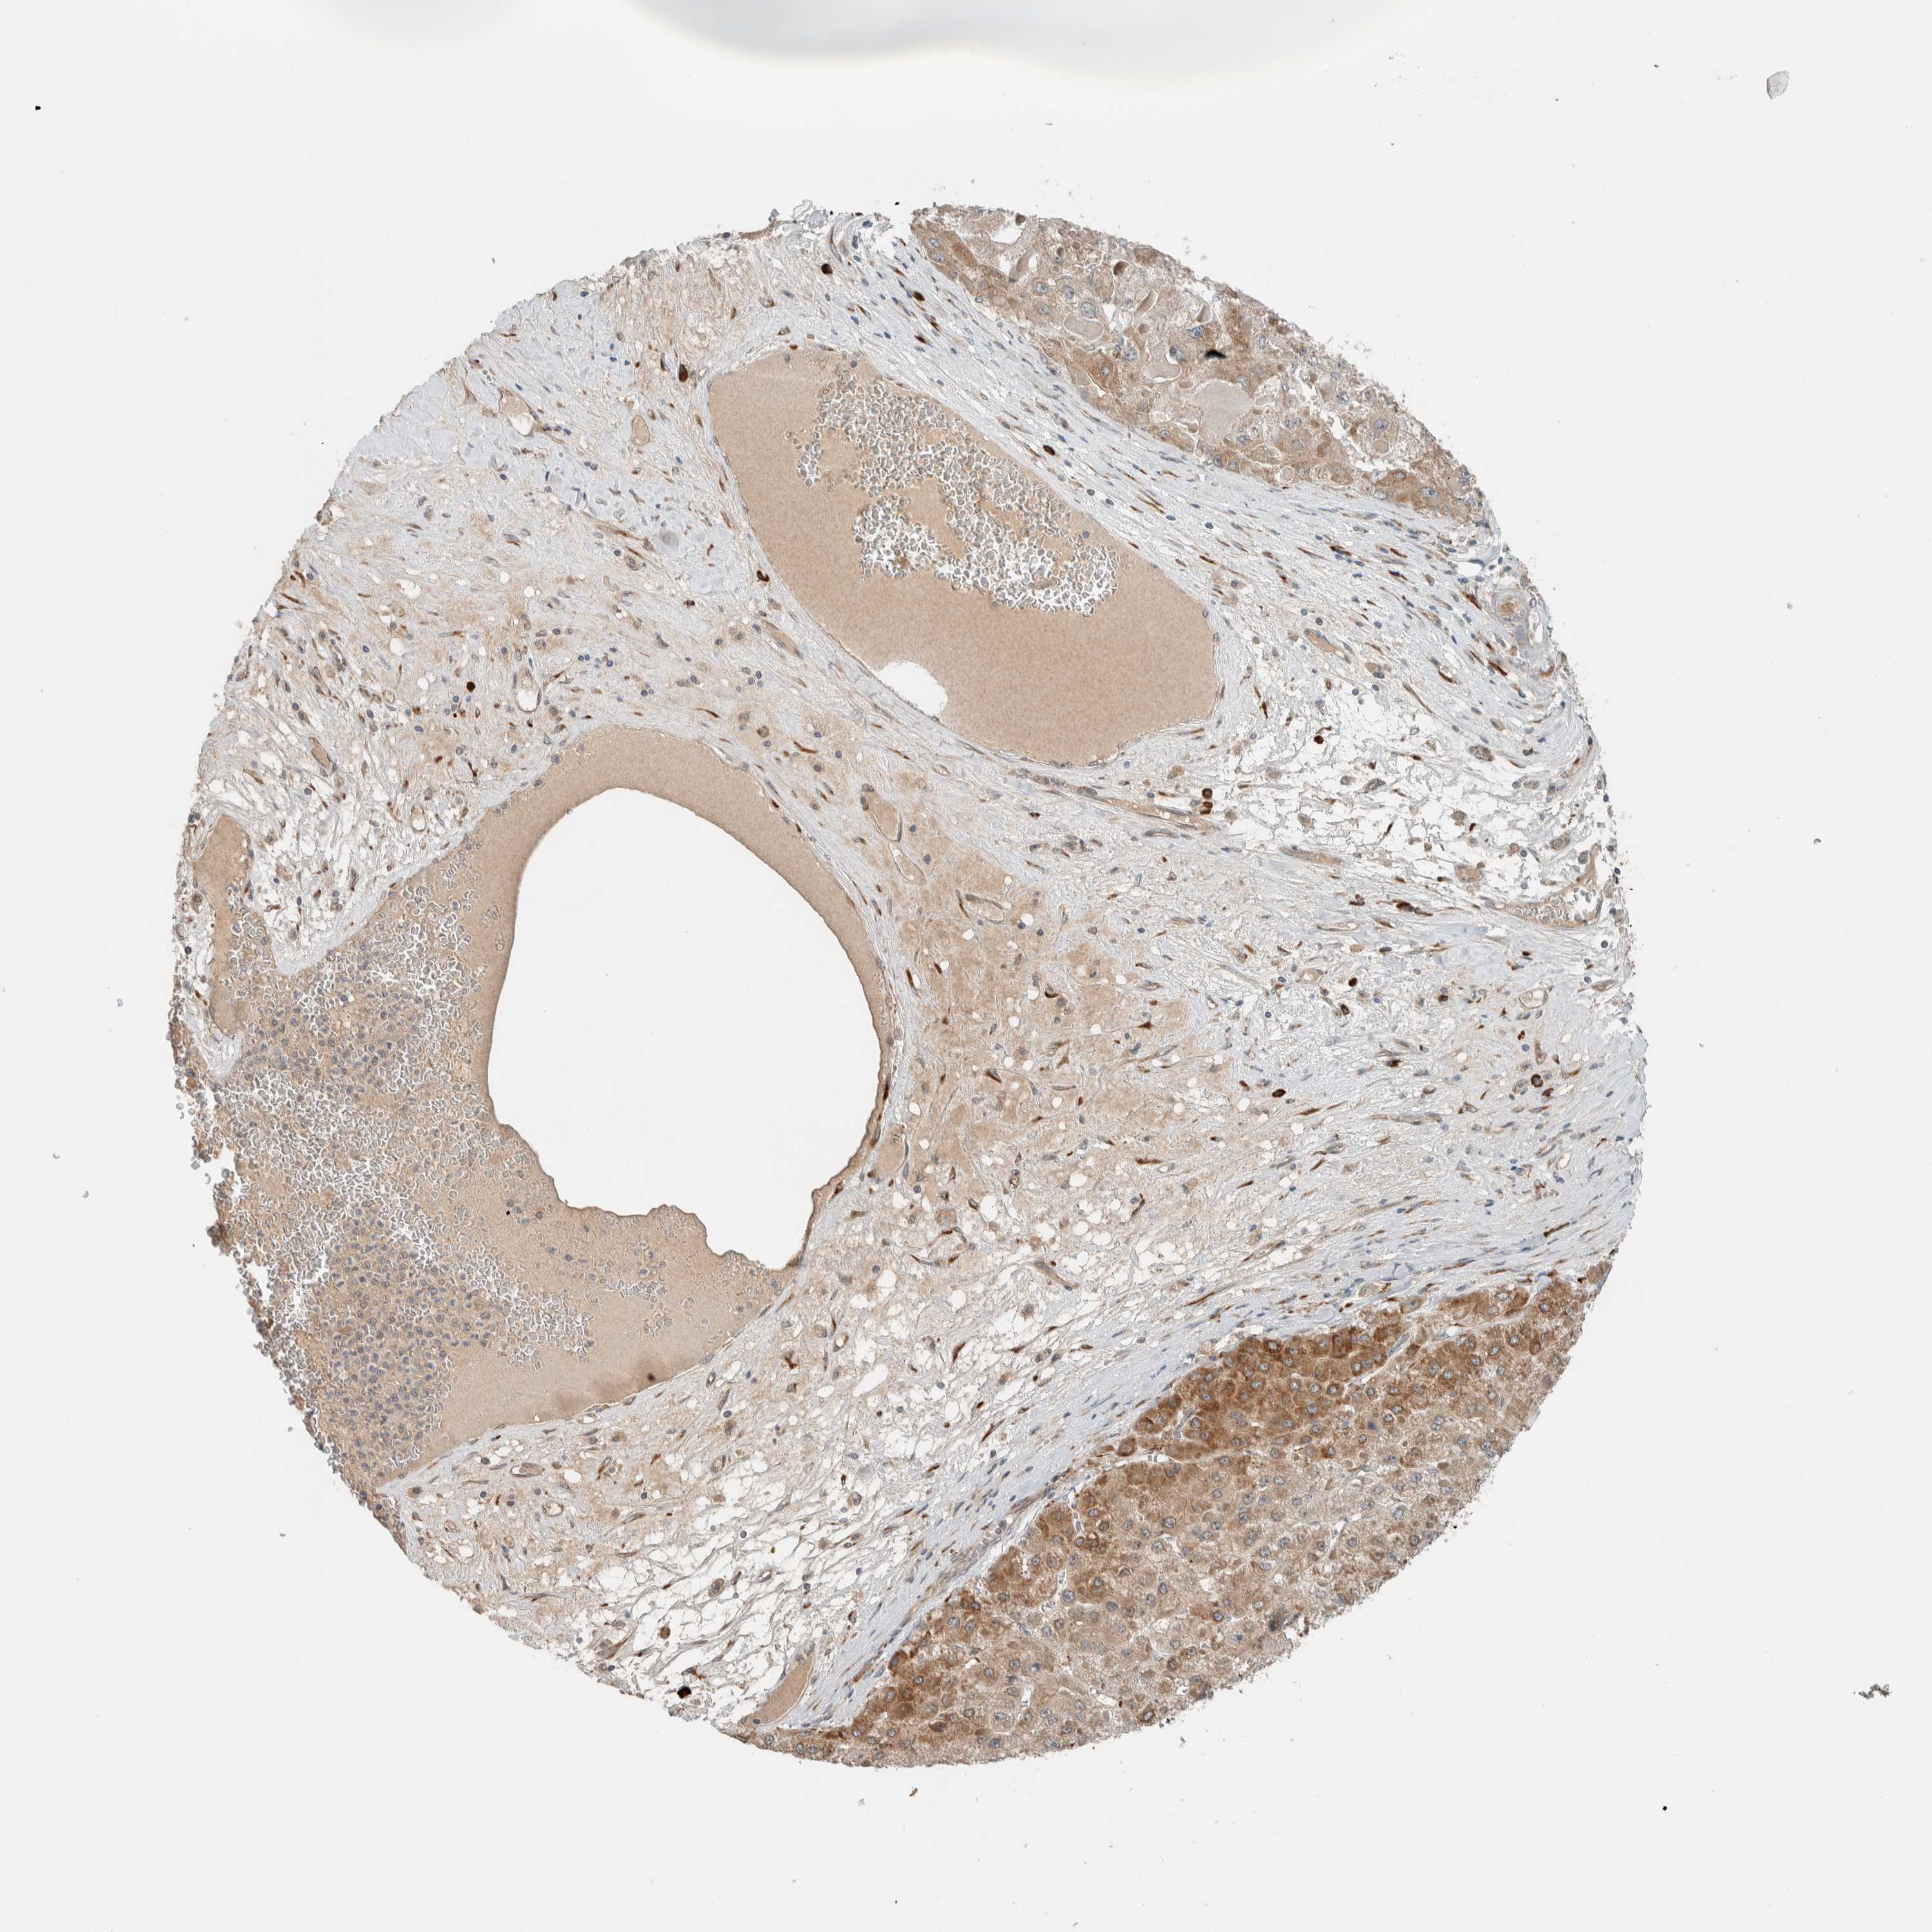

LIVER CANCER - Protein expressioni

A mouse-over function shows sample information and annotation data. Click on an image to view it in a full screen mode. Samples can be filtered based on level of antibody staining by selecting one or several of the following categories: high, medium, low and not detected. The assay and annotation is described here.

Note that samples used for immunohistochemistry by the Human Protein Atlas do not correspond to samples in the TCGA dataset.

Antibody stainingi

Antibody staining in the annotated cell types in the current human tissue is reported as not detected, low, medium, or high, based on conventional immunohistochemistry profiling in selected tissues. This score is based on the combination of the staining intensity and fraction of stained cells.

Each image is clickable and will lead to virtual microscopy that enables deeper exploration of all samples and also displays staining intensity scores, fraction scores and subcellular localization as well as patient and tissue information for each sample.

Antibody HPA023559

Antibody HPA023564

Antibody HPA044971

Antibody CAB031916

Staining

High

Medium

Low

Not detected

Intensity

Strong

Moderate

Weak

Negative

Quantity

>75%

75%-25%

<25%

None

Location

Nuclear

Cytoplasmic/membranous

Cytoplasmic/membranous,nuclear

Cholangiocarcinoma

Carcinoma, Hepatocellular, NOS